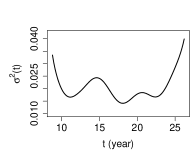

The estimated variance of the measurement error is by the method proposed in Section 3, by PACE and by LM, respectively. The estimates of the covariance surface are depicted in Figure 3. We observe that, the estimates produced by SNPTM and SNPTF are similar in the diagonal region, while visibly differ in the off-diagonal region. For this dataset, the upward off-diagonal parts of the estimated covariance surface by SNPTF seem artificial, so we recommend the SNPTM estimate for this data. For the PACE estimate, due to the missing data in the off-diagonal region and insufficient observations at two ends of the diagonal region, it suffers from significant boundary effect.

The mean function estimated by SNPTM111SNPTM, SNPTF and PACE use the same method to estimate the mean function. shown in the left panel of Figure 4 and found similar to its counterpart in Lin et al. (2019), suggests that the spinal bone mineral density increases rapidly from age 9 to age 16, and then slows down afterward. The mineral density has the largest variation around age 14, indicated by the variance function estimated by SNPTM222SNPTM and SNPTF use the same method to estimate the variance function. and shown in the middle panel of Figure 4. As a comparison, the PACE estimate, shown in the right panel of Figure 4, suffers from the boundary effect that is passed from the PACE estimate of the covariance function, because the PACE method estimates the variance function by the diagonal of the estimated covariance function.